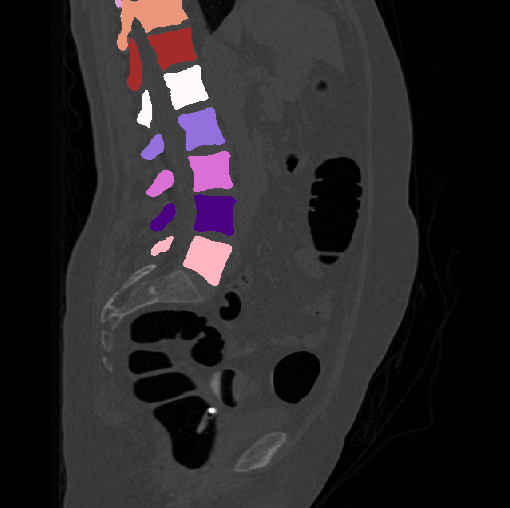

Images

GT

Predictions

We calculate the two metrics of each vertebra, and the results are reported in Table 2. On the one hand, our experimental results are close to those reported in reference (Sekuboyina et al., 2020) with the same model (nnUnet), verifying the high quality of our annotations. On the other hand, Table 2 shows it is difficult to segment the diseased vertebrae (the DSC of L6 is almost 0). Specifically, the existence of L6 confuses the model, resulting in prediction dislocations (see the last row in Fig. 4). Thus, our labeled dataset, which contains many L6 cases, is very valuable for the diseased vertebrae segmentation (we have stated those cases that are hard for annotation in the readme.txt file). Table 2 illustrates that the model trained with our annotations can achieve good performance on our CTSpine1K dataset but a much worse performance on the VerSe Challenge datasets, which explains there is an obvious domain gap between our annotated dataset and the public dataset. We infer the reason is that the COlONOG dataset is based on an empty stomach and colon, confusing the deep learning model by the changes of air content in the abdomen (see Fig. 3). Therefore, our annotations are a good complement to the existing datasets.

3.2.2 Qualitative results.

Some visualization results are presented in Fig. 4, where we can observe that the baseline model can achieve excellent segmentation results. Nevertheless, some failed predictions occur when spinal diseases exist, especially sacral lumbarization and lumbar sacralization. Besides, the image’s resolution of Z direction is closely related to the results, and a lower resolution leads to worse results. Maintaining a reasonable performance for a low resolution is a research challenge. Image superresolution (Peng et al., 2020) might be worth exploring.